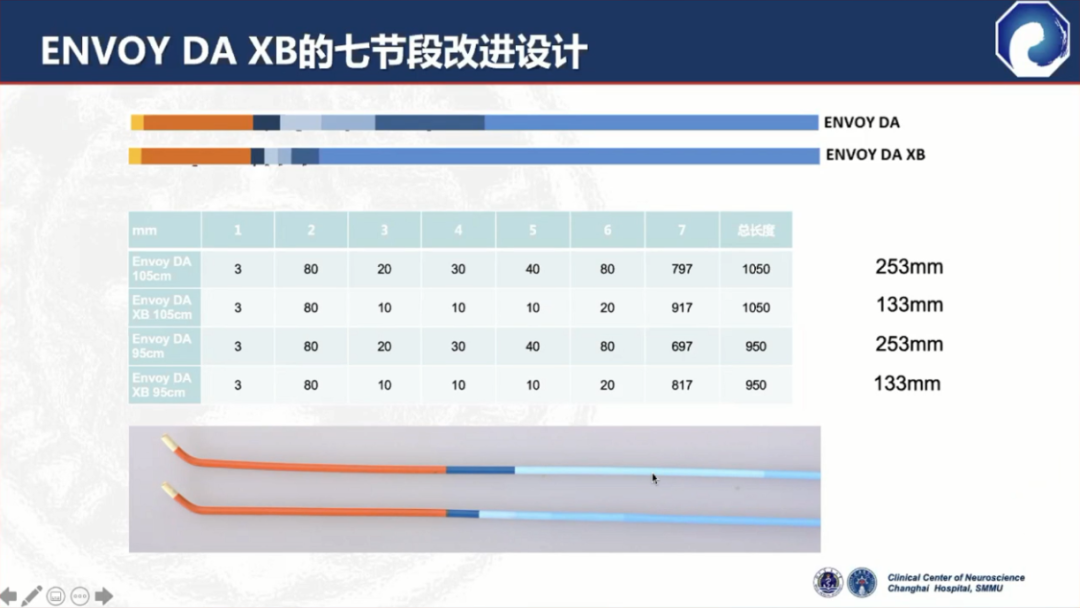

DA XB在DA的基础上做了改进,提升了支撑性